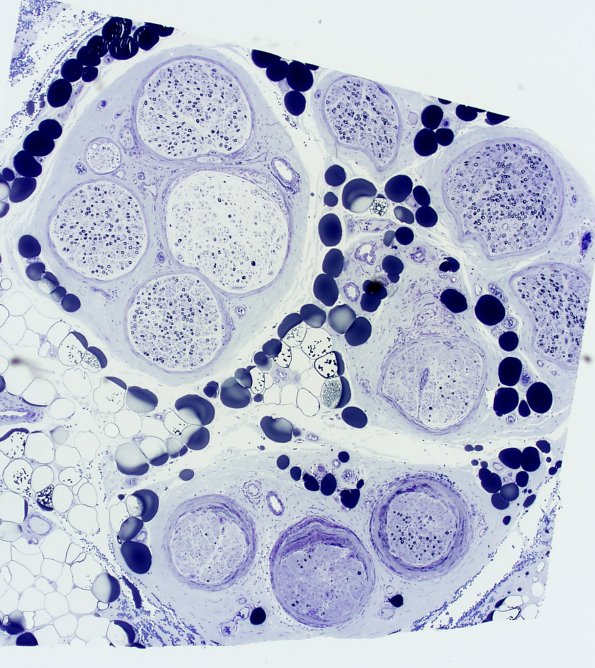

This low magnification image shows the patchy perineuritis in this nerve and the variability in the axonal density from fascicle-to-fascicle. (Plastic sections)